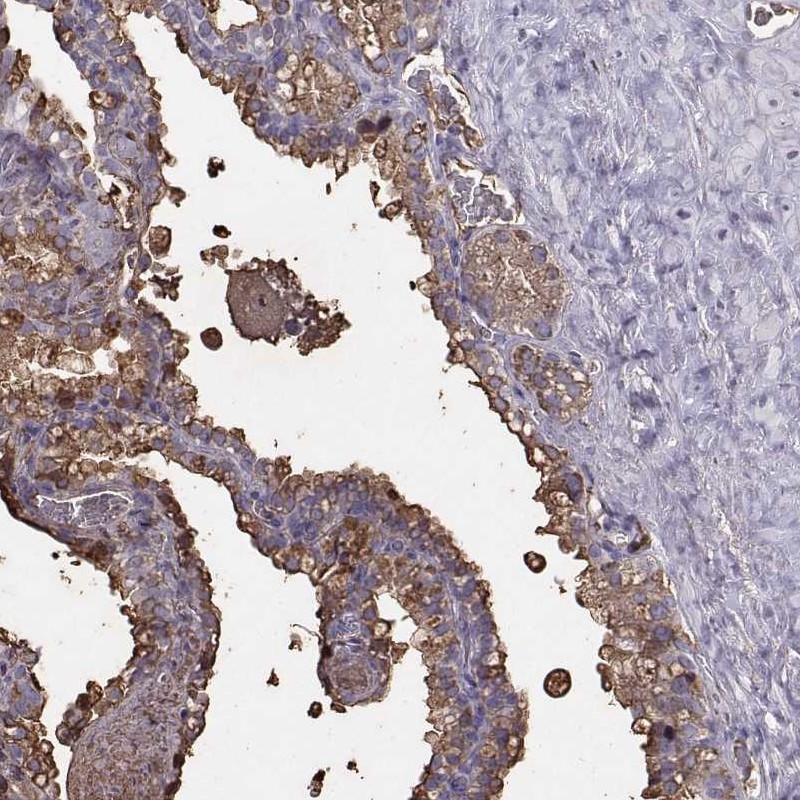

Immunohistochemistry analysis in human seminal vesicle and lymph node tissues using Anti-SEMG1 antibody. Corresponding SEMG1 RNA-seq data are presented for the same tissues.